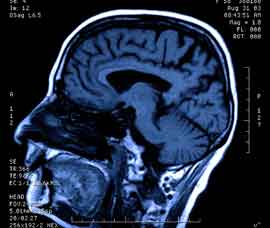

Motor neurone disease is a neurological disease that attacks nerves in the brain and spinal cord, causing muscles to waste over time. There is no cure for the disease that affects up to 5000 people in the UK, and the average life expectancy for most sufferers is 2-5 years after diagnosis.

Dr Radunovic said: “Messages from a motor neurone disease patient’s brain gradually stop reaching their muscles, which affects their speaking, walking, breathing, swallowing and general movement of the body. It’s a terrible disease because while the person’s mind remains perfectly intact, they are left unable to control many bodily functions.